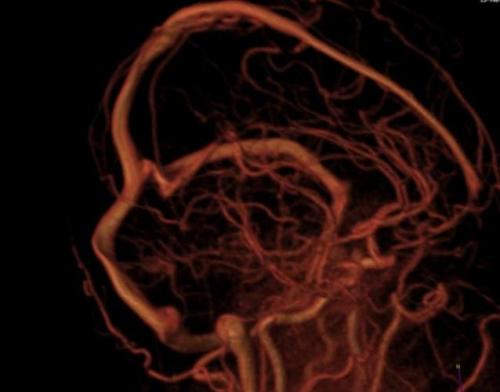

Исследование кровеносной системы применяют в хирургии, онкологии, неврологии и других направлениях медицины. МРТ заданной области с МР-ангиографией позволяет оценить функциональность, наполненность, просвет, состояние стенок вен и артерий.

По результатам сканирования определяют характер кровоснабжения рассматриваемой зоны, выявляют очаги ишемии, некроза. При травмах томограммы визуализируют гематомы, нарушение целостности сосудистой стенки.

Снижение тонуса, уменьшение просвета, разрывы стенок сосуда приводят к развитию патологических изменений в окружающих тканях и органах. Нарушение проходимости коронарных артерий вызывает деструктивные, дистрофические процессы сердечной мышцы, что может стать причиной инсульта или инфаркта.

Патологии аорты, верхней и нижней полой вены сопровождаются дисфункцией органов брюшной полости и малого таза, способствуют развитию заболеваний нижних конечностей.

В диагностике поражений сосудов головного мозга МРТ с использованием режима МР-ангиографии визуализирует малейшие изменения в работе кровеносной системы.

В МРТ существует два вида МР-ангиографии. Методы идентичны, различие заключается в цели исследования.

МРТ шеи с МР-ангиографией

Венография направлена на изучение работы одноименных сосудов. Сканирование позволяет диагностировать воспалительные, дегенеративные процессы, признаки реверсного (обратного) потока, определить причины патологических явлений.

Артериография показана в случае появления симптомов недостаточности кровоснабжения. При необходимости проводят комплексное исследование сосудистой системы.